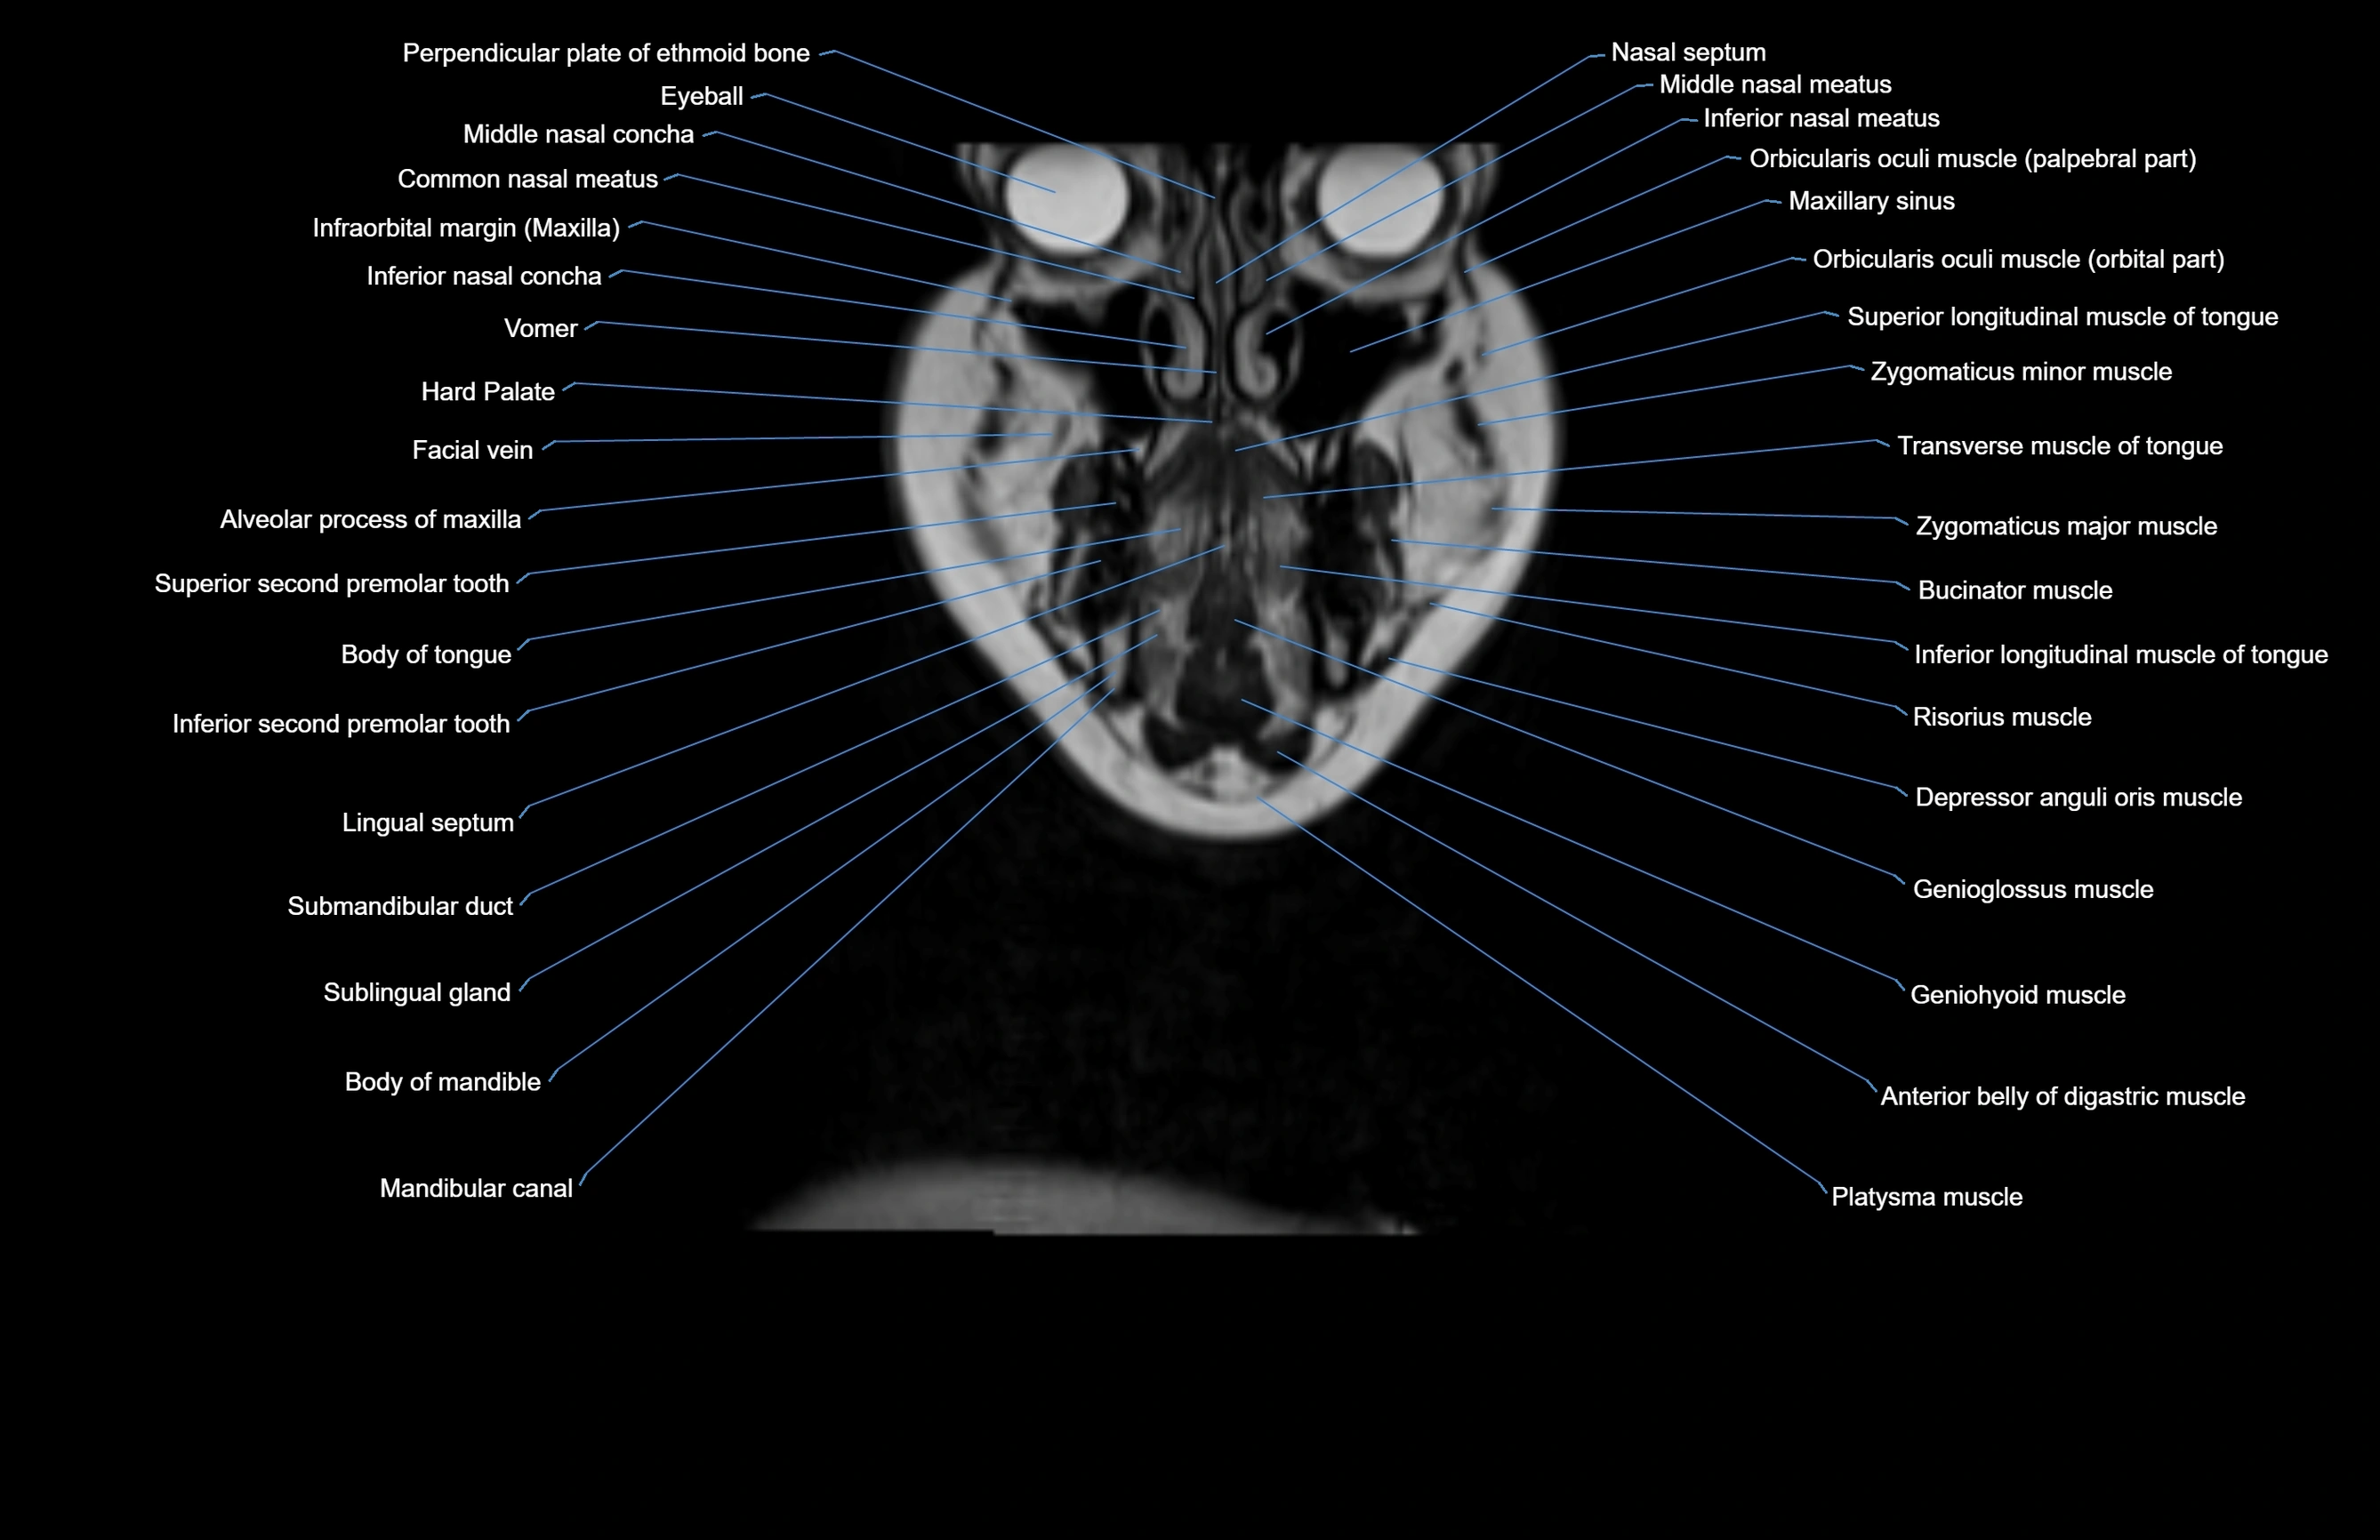

MRI images